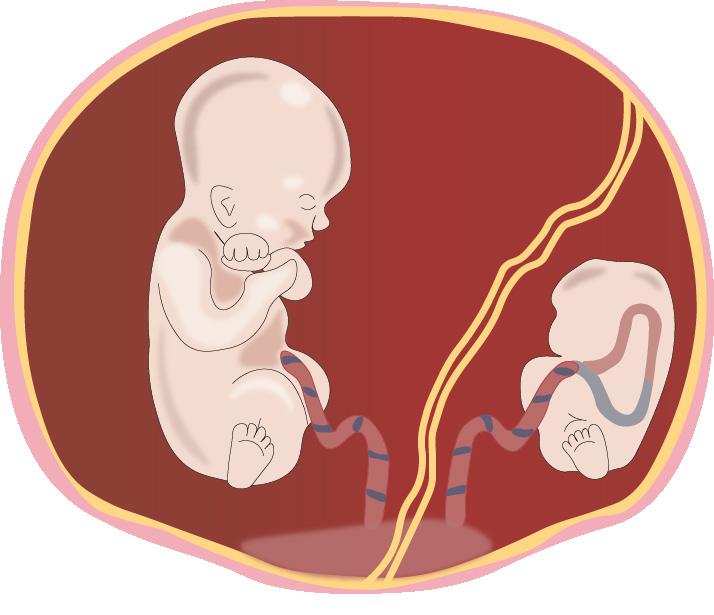

En embarazos dobles, se considera 1 gesta, 2 partos, en la mayoría de casos prematuros

Í NDICE 01 Desarrollo ovular Periodos del desarrollo del ser humano Teratogénesis Fisiología del embarazo pág. 75 Requerimiento calórico 02 pág. 85 Atención prenatal Factores de riesgo obstétrico Propedéutica obstetrica Nutrición en el embarazo 03 pág. 87 Evaluación gestacional Fisiología y periodos Periodo dilatación y movimientos cardinales Parto eutócico 04 pág. 99 Generalidades Distocias 05 pág. 105 Parto distócico VIH Tuberculosis Diabetes gestacional 06 pág. 113 Enfermedades intercurrentes del embarazo Corioamnionitis Infección del tracto urinario (ITU) Endometritis puerperal 07 pág. 119 Infecciones en obstetricia 11 Clasificación Fármacos teratógenos Fármacos y tóxicos pág. 145 Periodo expulsivo Mastitis purperal Inducción de trabajo de parto Exploración abdominal Diámetros fetales Oligohidramnios Polihidramnios 08 pág. 125 Patología del líquido amniótico Hiperémesis gravídica Parto pretérmino Anemia y gestación 09 pág. 127 Complicaciones obstétricas Hipertensión crónica Hipertensión gestacional 10 pág. 139 Estados hipertensivos del embarazo Micronutrientes Ganancia ponderal Pelvimetría Diagnóstico de cromosomopatías Ecografía obstétrica Periodo alumbramiento Parto Cesárea Embarazo postérmino Preeclampsia Diagnóstico Cambios fisiológicos Hormonas de la gestación Anexos fetales Monitoreo fetal Gestación múltiple Ruptura prematura de membranas (RPM) Restricción del crecimiento intruterino (RCIU) Isoinmunización RH

La ecografía de I trimestre determina la corionicidad en el caso de gestaciones múltiples y tamizaje para cromosomopatías.